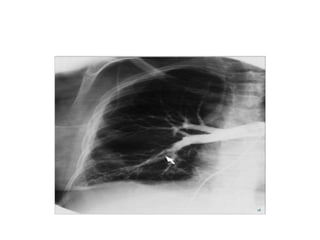

Chest Radiography

• A near-normal radiographic appearance in the setting of

severe respiratory compromise is highly suggestive of massive

PE.

• Major chest radiographic abnormalities are uncommon.

• Focal oligemia (Westermark sign) indicates massive central

embolic occlusion.

• A peripheral wedge-shaped density above the diaphragm

(Hampton hump) usually indicates pulmonary infarction.

• A subtle abnormality suggestive of PE is enlargement of the

descending right pulmonary artery.

• The chest radiograph also can help identify patients with

diseases that mimic PE, such as lobar pneumonia and

pneumothorax, but patients with these illnesses also can have

concomitant PE.